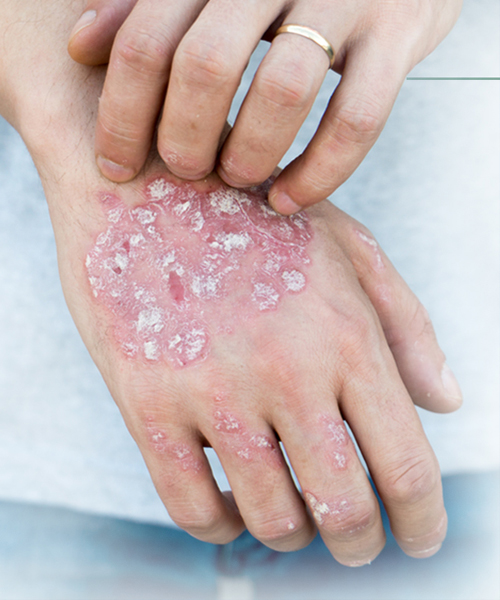

Signs and Symptoms

- Inflammation